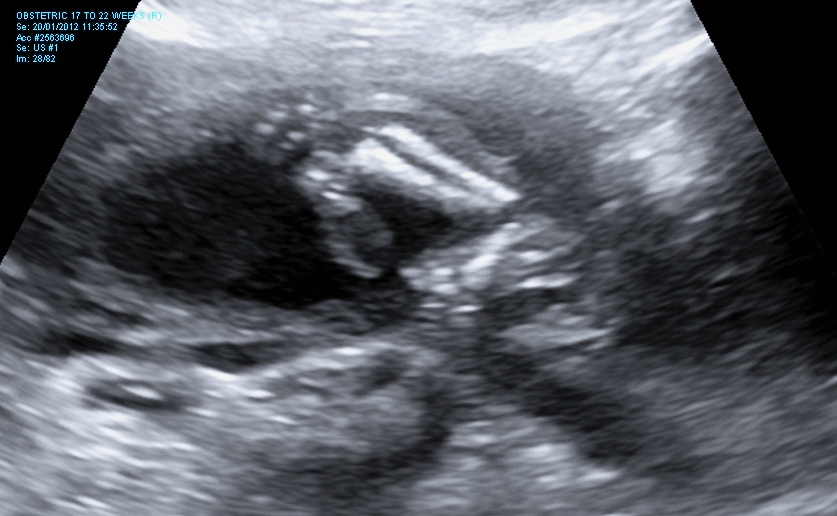

I finally managed to get hold of my u/s disc and have selected a few of the pics I think could have a nub in them (I'm still pretty hopeless at working out nubs).

I have included quite a few from my early scan but bub was 11w4d so I understand prob slightly early still.